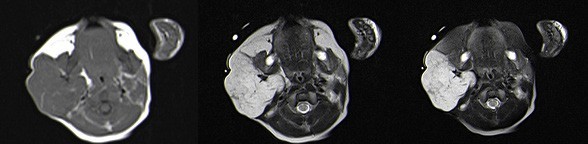

Na RM, identificou-se assimetria do volume das parótidas, por marcado aumento da direita, devido a lesão interessando os seus lobos superficial e profundo, de contornos regulares e limites bem definidos, com maior eixo de 48 mm (Figs. 3 e 4). A extensão da lesão ao lobo profundo da glândula parótida direita determinava desvio medial da gordura parafaríngea, sem repercussão sobre o contorno da coluna aérea faríngea. Apesar das características semiológicas por imagem da lesão parotídea direita não serem específicas, atendendo às características clínicas da alteração cutânea apresentada pela examinada na mesma região, considerou-se a hipótese diagnóstica mais provável de hemangioma infantil misto. Na apreciação sumária do parênquima encefálico conseguida não se identificaram aspetos malformativos, em particular da fossa posterior, nem aspetos suspeitos de hemangiomas intracranianos.

Figura 4: RM, cortes axiais, com ponderações em T1, T2 e T2 FS: traduzida por sinal intermédio em T1 e hipersinal em T2 e T2 FS, sendo possível individualizar alguns sinais de vazio vascular no seu interior. Extensão da lesão ao lobo profundo da glândula parótida direita determinava desvio medial da gordura parafaríngea homolateral.